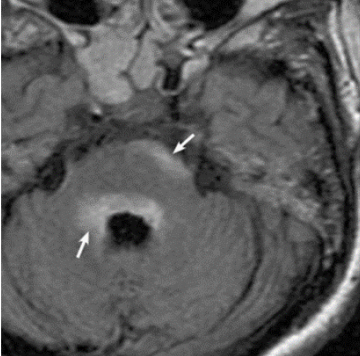

Перечисленная симптоматика может говорить и о других заболеваниях, поэтому острый стволовой синдром диагностируется после проведения магнитно-резонансной томографии. На снимках можно увидеть поражения в периэпендимальных отделах ствола мозга, включая мост.

Острый стволовой синдром при ЗСОНМ МРТ в режиме FLAIR в аксиальной плоскости демонстрирует периэпендимальные поражения ствола мозга, включая мост (белые стрелки)1